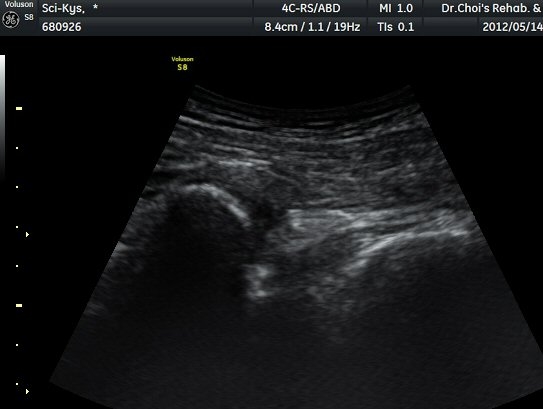

¾ûµ¢ÀÌ Á°ñ¿¡¼­ Á°ñ½Å°æ Ⱦ´Ü¸é°Ë»ç¿¡¼­ ´ëµÐ±Ù°ú quadratus femoris »çÀÌÀÇ ±Ù¸·

°æ°èºÎ¿¡¼­ Á°ñ½Å°æÀÌ °üÂûµÇ´Âµ¥ ³»Ãø Á°ñ°áÀý(ischial tuberosity) ÃøÀ¸·Î Ä¡¿ìÃÄ

ÀÖ´Â °ÍÀ¸·Î ÆÇ´ÜµÈ´Ù(±×¸² 1, 2, 3).

Á¤»óÃø(±×¸² 6, 7)°ú ºñ±³Çϸé Á°ñ½Å°æÀÇ ³»Ãø ÀüÀ§°¡ ¶Ñ·ÈÇÏ´Ù.